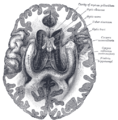

العصب البصريOptic Nerve : هو الزوج الثاني من الأعصاب القحفية الاثني عشر، وهو عصب حسي ينشأ من الخلايا العقدية للشبكية، وتتجمع أليافه في حلمة العصب البصري، ويخرج من كرة العين إلى جوف الحَجاج ثمّ إلى جوف القحف عبر النفق البصري حتى التقاطع البصري وينتهي في النواة الركبية الوحشية.[1]

العصب البصري هو الجزء الثاني من اثني عشر زوجا من العصب القحفي لكنه يعتبر جزءا من الجهاز العصبي المركزي لأنه مستمد التي تنتجها خلايا oligodendrocytes بدلا من خلايا شوان في الجهاز العصبي الطرفي وهي مغطاه داخل السحايا. ولذلك تسميته بالـ"عصب" من الناحية الفنية هي تسمية خاطئة، لأن النظام البصري جزء من النظام العصبي المركزي والأعصاب موجودة، بحكم التعريف، داخل النظام العصبي الطرفي. لذلك الأعصاب الطرفية مثل متلازمة غيان باريه ، لا تؤثر على العصب البصري.

العصب البصري ensheathed (مغطى بالمايلين)في جميع الطبقات الثلاث سحائي (الجافية، arachnoid، والأم الحنون) بدلا من epineurium، perineurium، وendoneurium الموجود في الأعصاب الطرفية. مسارات الألياف في الثدييات في الجهاز العصبي المركزي (على العكس من النظام العصبي الطرفي) غير قادرة على التجدد وبالتالي تلف العصب البصري ينتج عمى لا رجعة فيه. الألياف من شبكية العين تسير على طول العصب البصري إلى تسع نويات بصرية أولية في المخ، حيث المدخلات الرئيسية تدخل إلى القشرة البصرية الأولية.

العصب البصري يتألف من محاور عقد عصبية للشبكية وخلايا Portort. وهو يترك المدار (العين) عبر القناة البصرية ،بشكل postero-medially تجاه chiasm البصرية حيث يوجد partial decussation من الألياف من حقول البصرية للأنف من كلتا العينين. معظم المحور العصبية للعصب البصري تنتهي في lateral geniculate nucleus حيث المعلومات تنتقل إلى القشرة البصرية، في حين أن المحاور العصبية الأخرى تنتهي في الـ pretectal nucleus وتشارك في حركات العين الانعكاسية ومحاور عصبية أخرى تنتهي في suprachiasmatic nucleus وتتدخل في تنظيم دورة النوم واليقظة. ويزيد قطرها حوالي 1.6 ملم من داخل العين، إلى 3.5 ملم في المدار إلى 4.5 ملم داخل فضاء الجمجمة. وأطوال مكونات العصب البصري 24 ملم في المدار، 9 ملم في القناة البصرية و 16 مم في فضاء الجمجمة قبل أن ينضم إلى chiasm البصرية. هناك ،يحدث الـ decussation الجزئي وحوالي 53 ٪ من الألياف تتشابك لتكون الـ optic tracts. معظم هذه الألياف تنتهي في جسم geniculate الأفقي.[2]